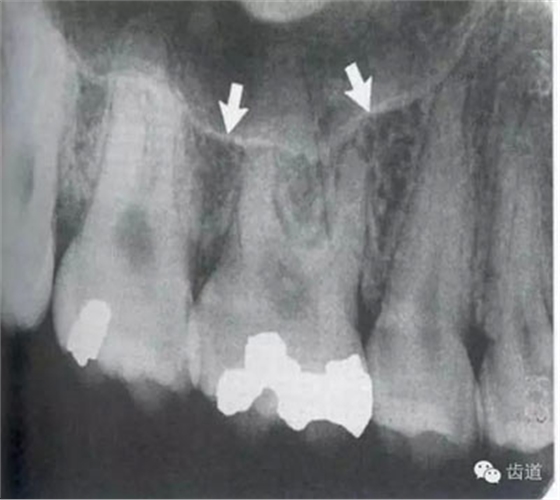

在投照上頜磨牙根尖片時(shí),經(jīng)常可以看到牙根上方有一密度低的影像,為上頜竇的一部分,邊緣環(huán)繞以密度高的線狀影像,為上頜竇壁致密骨層。有時(shí)可見(jiàn)上頜竇的分隔。